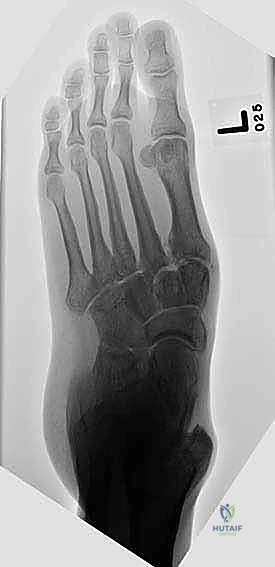

- الأشعة السينية أثناء الوقوف (Weight-bearing X-rays): وهي أهم أداة تشخيصية. الأشعة العادية والسرير فارغ لا تظهر المشكلة الحقيقية؛ يجب التقاط الأشعة والمريض يقف ليتحمل وزن الجسم، مما يظهر الانهيار الفعلي للمفاصل وتضيق المسافات بين العظام.

- الأشعة المقطعية (CT Scan): توفر صوراً ثلاثية الأبعاد للعظام، وهي ضرورية جداً للتخطيط الجراحي الدقيق وتحديد مدى التلف العظمي والزوايا المطلوبة للتثبيت.